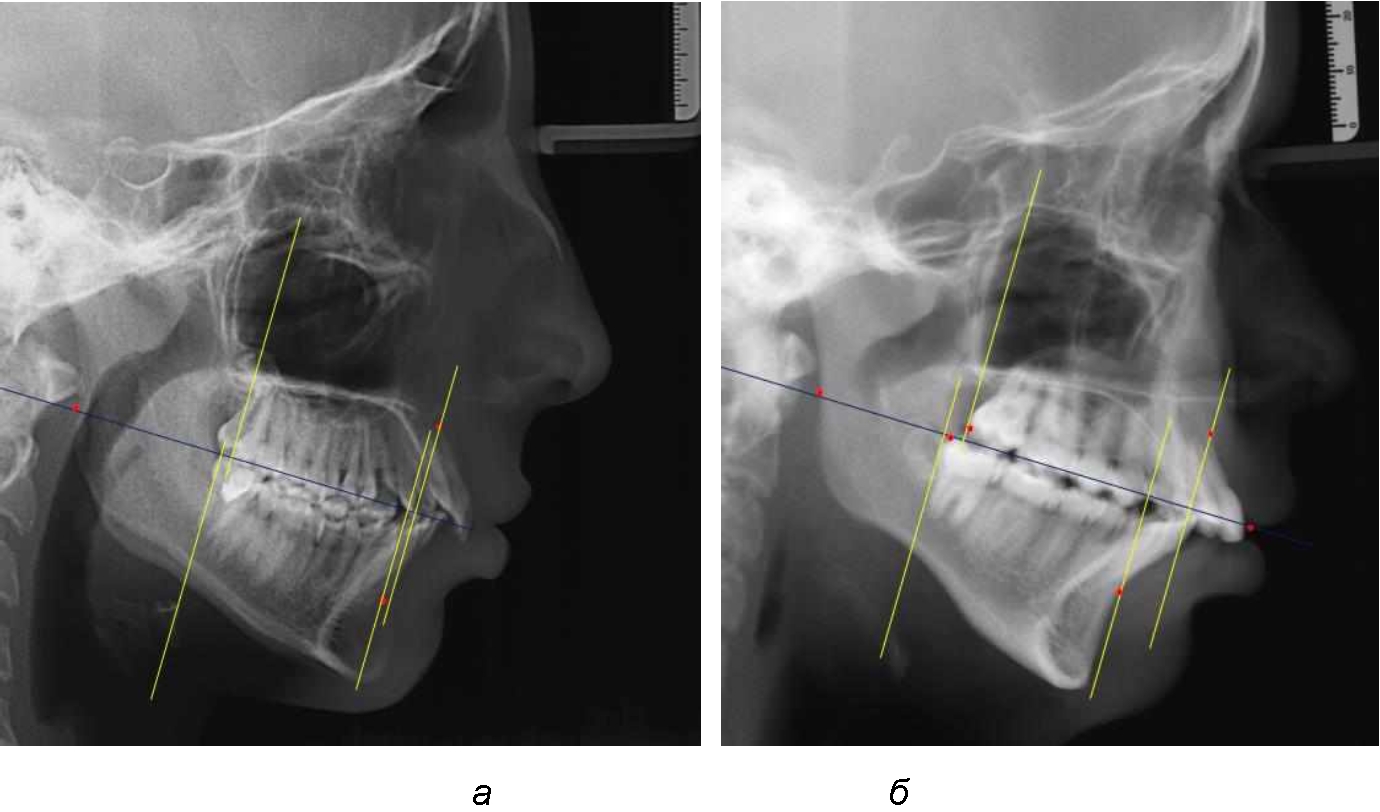

При сагиттальной патологии прикуса встречались варианты, при которых отмечалось равенство либо не равенство альвеолярно-ден-тальных размеров челюстей. Однако вне зависимости от этого, как правило, была отмечена разница в положении челюстей, измеряемая от конструируемой точки «rmРOcP» до точек апикальных базисов по Downs. С дистальной окклюзией было 20 снимков и с мезиальной окклюзией – 19 снимков.

Характерной особенностью мезиальной окклюзии было увеличение расстояния между проекционными апикальными точками, при котором существенно смещалась кпереди нижняя челюсть, а Wits-число имело отрицательные значения. Также дистальная точка нижнего моляра была расположена кпереди от верхней дистальной точки окклюзии второго моляра. Относительно равными считались показатели альвеолярно-дентальных размеров, при которых разница не превышала 1,5 мм. Тем не менее расстояние «rmРOcP-B(SM)» превышало расстояние «rmРOcP-A(SS)» в среднем по группе на (6,87 ± 1,62) мм, что свидетельствовало об аномалии положения челюстей, при котором визуально нижняя челюсть располагалась впереди верхней челюсти (рис. 3).

Рис. 3. Положение апикальных точек и челюстей при мезиальной окклюзии с равными (а) и разными (б) альвеолярно-дентальными размерами зубо-челюстных дуг

В тех случаях, когда при мезиальной окклюзии альвеолярно-дентальные размеры были различными, размер нижней челюсти превышал аналогичный параметр верхней челюсти в среднем на (3,74 ± 1,28) мм.